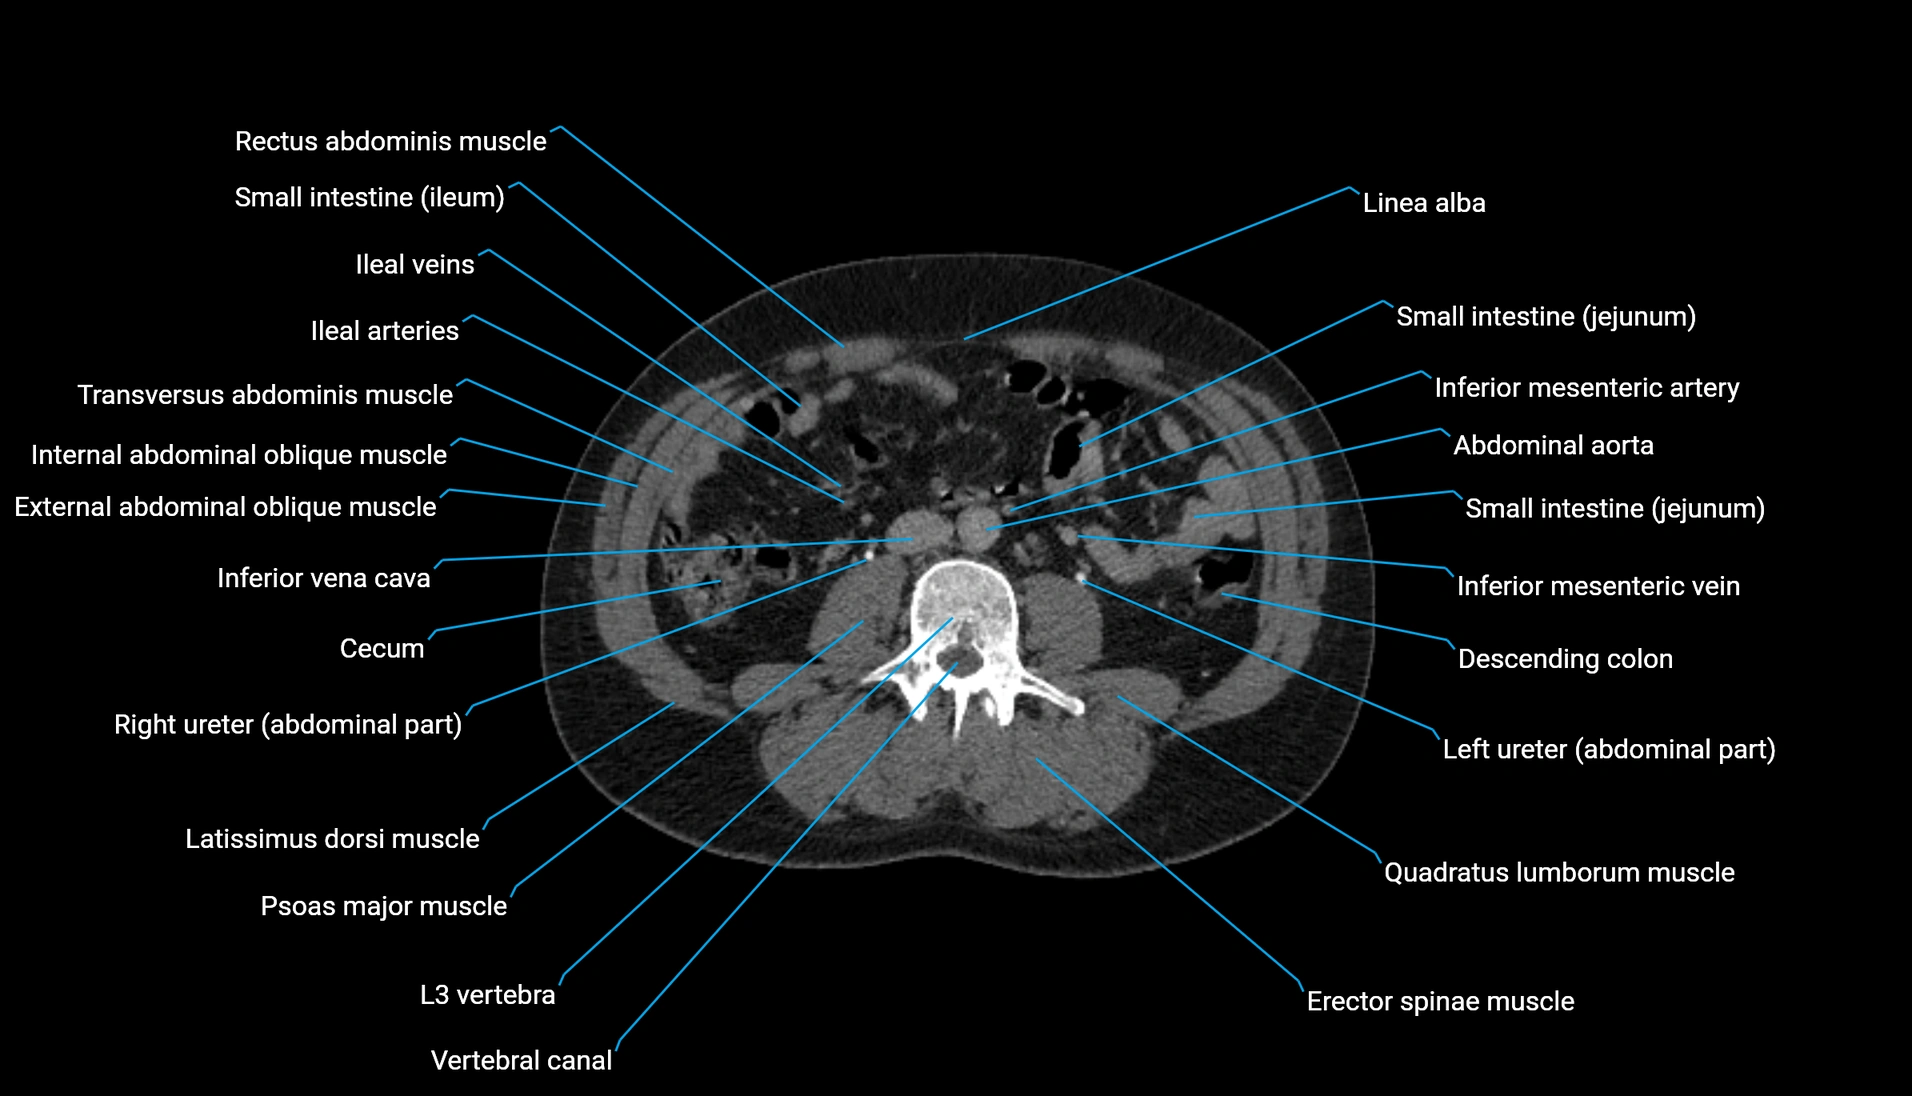

CT Appearance

Non-contrast CT:

-

Demonstrates cortical bone of acetabular rim in excellent detail

Detects fractures, dysplasia, retroversion, or bony overcoverage (pincer impingement)

3D reconstructions used in preoperative hip surgery planning

CT VRT 3D image